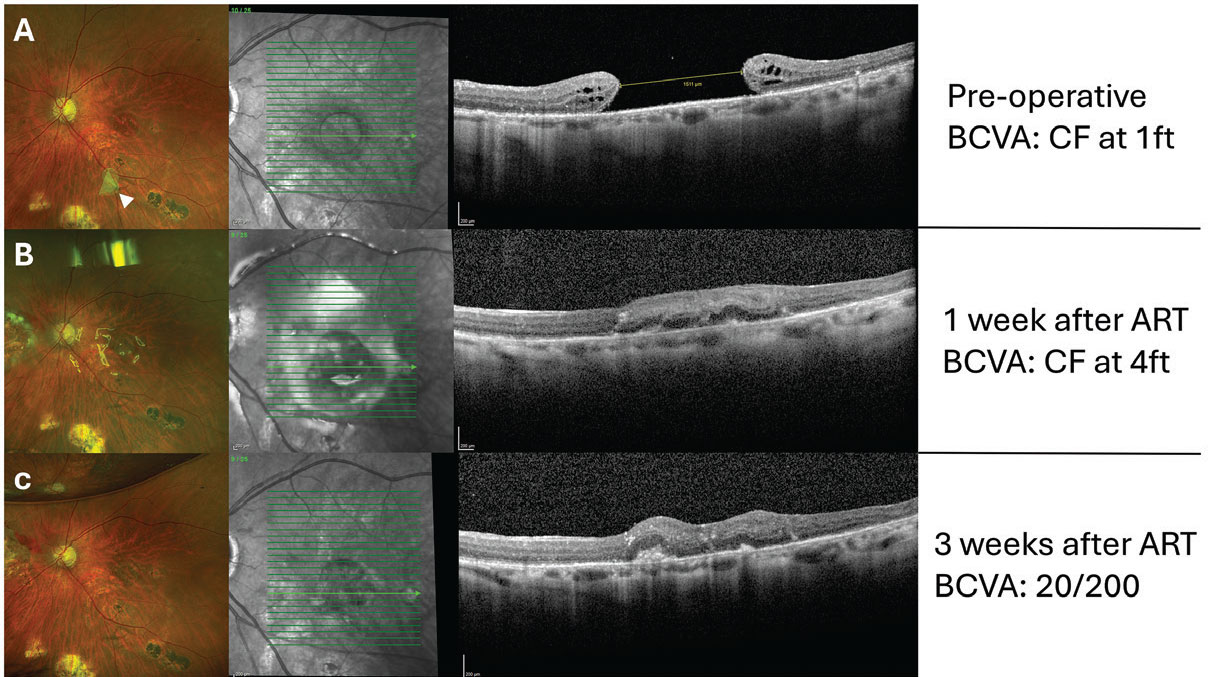

| Figure 2. (A) Preoperative OCT of a giant macular hole (minimum hole diameter: 1,511 µm) in a patient with multiple failed prior surgeries, including ILM peeling, macular hole border hydrodissection with BSS and amniotic membrane transplantation. Preoperative visual acuity was counting fingers at 1 foot, with a large central scotoma. The white arrowhead indicates the displaced amniotic membrane after intraocular gas reabsorption. (B) One week post-autologous retinal transplant, with perfluorocarbon heavy liquid as a temporary tamponade. Initial graft integration is observed and visual acuity improved to counting fingers at 4 feet. (C) Three weeks post-ART. PFCL was removed two weeks after ART, and air was used as tamponade for the second surgery. OCT shows further graft integration at the hole’s border, with BCVA improving to 20/200. The patient also reported a significant reduction in the central scotoma. |